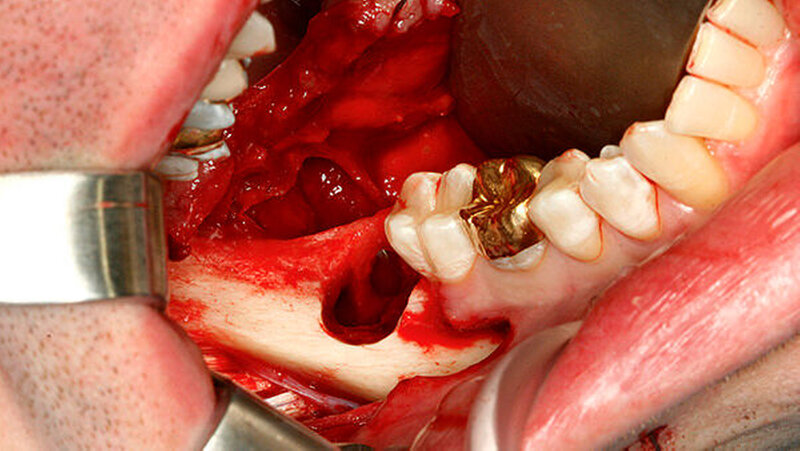

Zur bildgebenden Diagnostik erfolgten ein Orthopantomogramm und alio loco eine Zahnfilmaufnahme, bei der sich der dislozierte Wurzelrest des Zahnes 48 circa 3 mm kaudal der Alveole projizierte. In der durchgeführten digitalen Volumentomografie stellte sich der Wurzelrest kaudal der Linea mylohyoidea und medial der Tuberositas pterygoidea im Bereich der rechten Submandibularloge dar (Abbildungen 1 bis 4). Die operative Entfernung des Wurzelrests erfolgte durch einen transoralen Zugang in nasotrachealer Intubationsnarkose. Als operativen Zugang in den posterolateralen Mundboden beziehungsweise in die Submandibularloge rechts wurde der bestehende gingival geführte Winkelschnitt durch einen lingualen Zahnfleischrandschnitt aus regio 47 bis 43 sowie durch eine transversale Verbindung disto approximal 47 erweitert. Die daraus resultierende H-förmige Schnittführung erlaubte die subperiostale Darstellung des Ramusvorderrands und das retrograde (von der Koronoidkerbe ausgehende) Auslösen des lingualen Weichgewebes zur Bildung eines lingualen Mukoperiostlappens. Nach stumpfer Präparation einer Kavität entlang der lingualen Innenkortikalis und um die konvexe Kontur des retromolaren Knochenbalkons bis auf die Kranialfläche des M. mylohyoideus wurde der Muskel im Dorsalbereich seiner Insertionslinie mit der Schere scharf abgetrennt, um die Submandibularloge von kranial zu eröffnen. Die Retraktion des Mukoperiostlappens nach intermaxillär führte zur übersichtlichen Exposition der gesamten Retromolarregion und der Möglichkeit, unter Schonung des N. lingualis in die Submandibularloge einzugehen (Schnittführung siehe Abbildung 5). Im lingualen Kortex der Alveole regio 48 wurde eine Perforation in den Mundboden von etwa 6 bis 7 mm Durchmesser als Durchtrittsstelle für den Wurzelrest identifiziert (Abbildung 6).

Da von transoral keine direkte Sicht ins Spatium submandibulare möglich war, wurde das Wurzelfragment 48 mit dem Zeigefinger palpiert und mit einer stumpfen gebogenen Klemme und der Fingerbeere entfernt (Abbildung 7). Das kleinere Kortikalisfragment ließ sich digital identifizieren und in gleicher Weise entfernen. Nach Reposition der Weichteile erfolgte ein mehrschichtiger Wundverschluss mit Einzelknopfnähten, zirkumdentalen Nähten und einer Tabaksbeutelnaht regio 37 zur Refixierung des lingualen Mukoperiostlappens. Der postoperative Verlauf gestaltete sich unter perioperativer Antibiose komplikationslos. Die postoperativen radiologischen Kontrollaufnahmen (Orthopantomogramm, Zahnfilm) ergaben keinen Hinweis auf ein verbliebenes Zahnfragment.